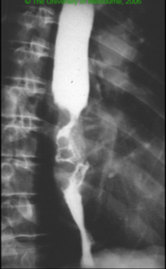

66yo patient presents with dysphagia to solids and liquids. This is aided by postural change. Associated history of mild, ongoing weight loss and regurgitation

Achalasia